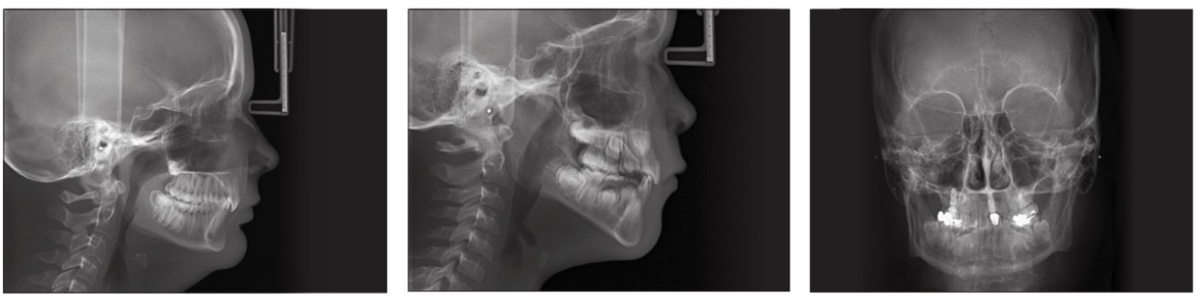

• Телерентгенограмма (ТРГ) в боковой, фронтальной проекции черепа

• Рентгенограмма придаточных пазух носа, лицевого отдела черепа

ТРГ в стоматологии – важный этап подготовки к ортодонтическому лечению, а в ортопедии – при функциональной диагностике пациентов, вмешательствах в челюстно-лицевой хирургии и травматологии.

Рентгенограмма придаточных пазух носа дает широкие возможности для постановки и подтверждения различных заболеваний околоносовых синусов. Полученные снимки помогают врачам визуализировать лобные

и верхнечелюстные пазухи, решетчатый лабиринт, глазницы и кости лицевого черепа.

Рентгенограмма придаточных пазух носа дает широкие возможности для постановки и подтверждения различных заболеваний околоносовых синусов. Полученные снимки помогают врачам визуализировать лобные и верхнечелюстные пазухи, решетчатый лабиринт, глазницы и кости лицевого черепа.